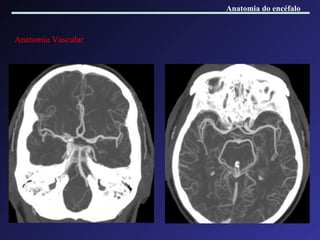

Anatomia Vascular Anatomia do encéfalo